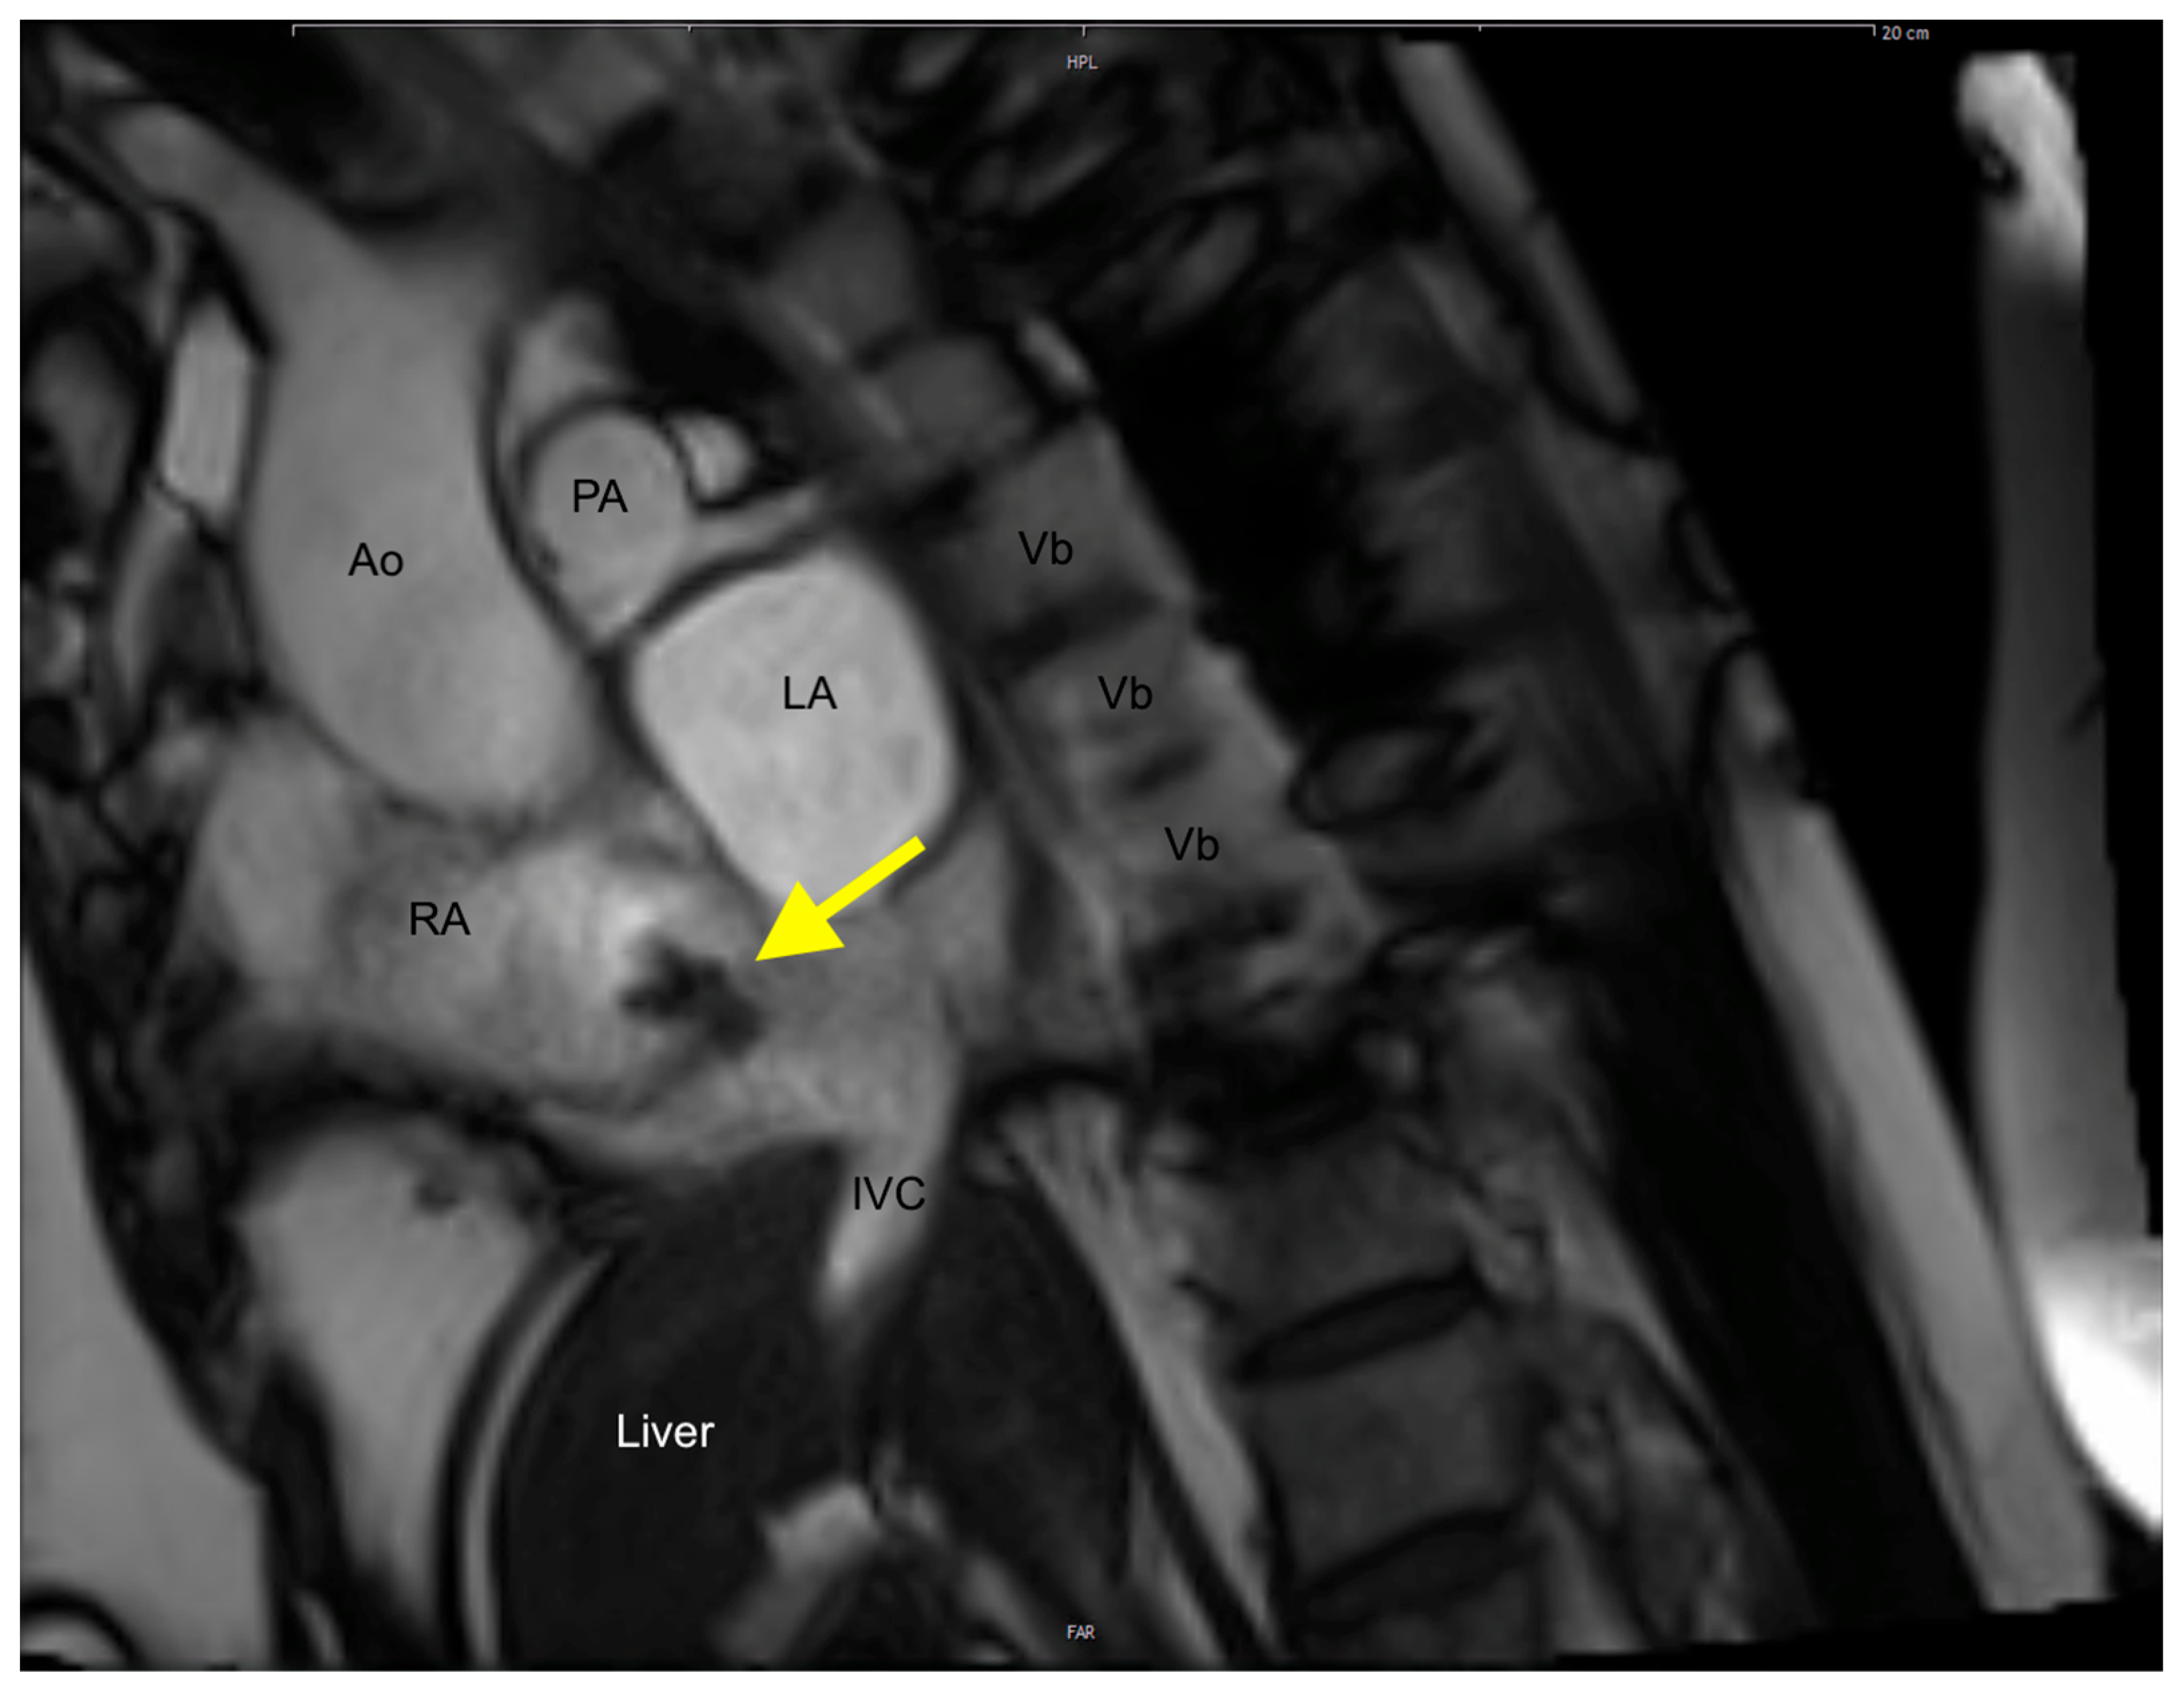

2. Case Presentation